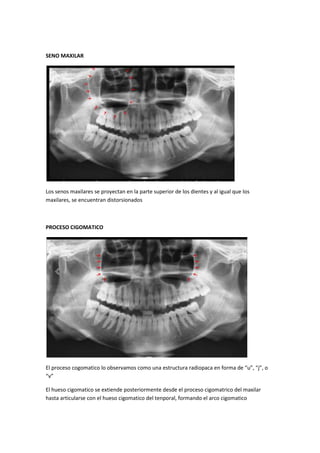

SENO MAXILAR

Los senos maxilares se proyectan en la parte superior de los dientes y al igual que los

maxilares, se encuentran distorsionados

PROCESO CIGOMATICO

El proceso cogomatico lo observamos como una estructura radiopaca en forma de “u”, “j”, o

“v”

El hueso cigomatico se extiende posteriormente desde el proceso cigomatrico del maxilar

hasta articularse con el hueso cigomatico del tenporal, formando el arco cigomatico